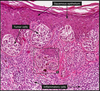

Describe picture

HPV cytopathic effect (koilocytic atypia) characterized by atypical, enlarged, hyperchromatic nuclei with perinuclear halos

Describe picture

Papillary, exophytic, treelike cores of stroma covered by thickened squamous epithelium